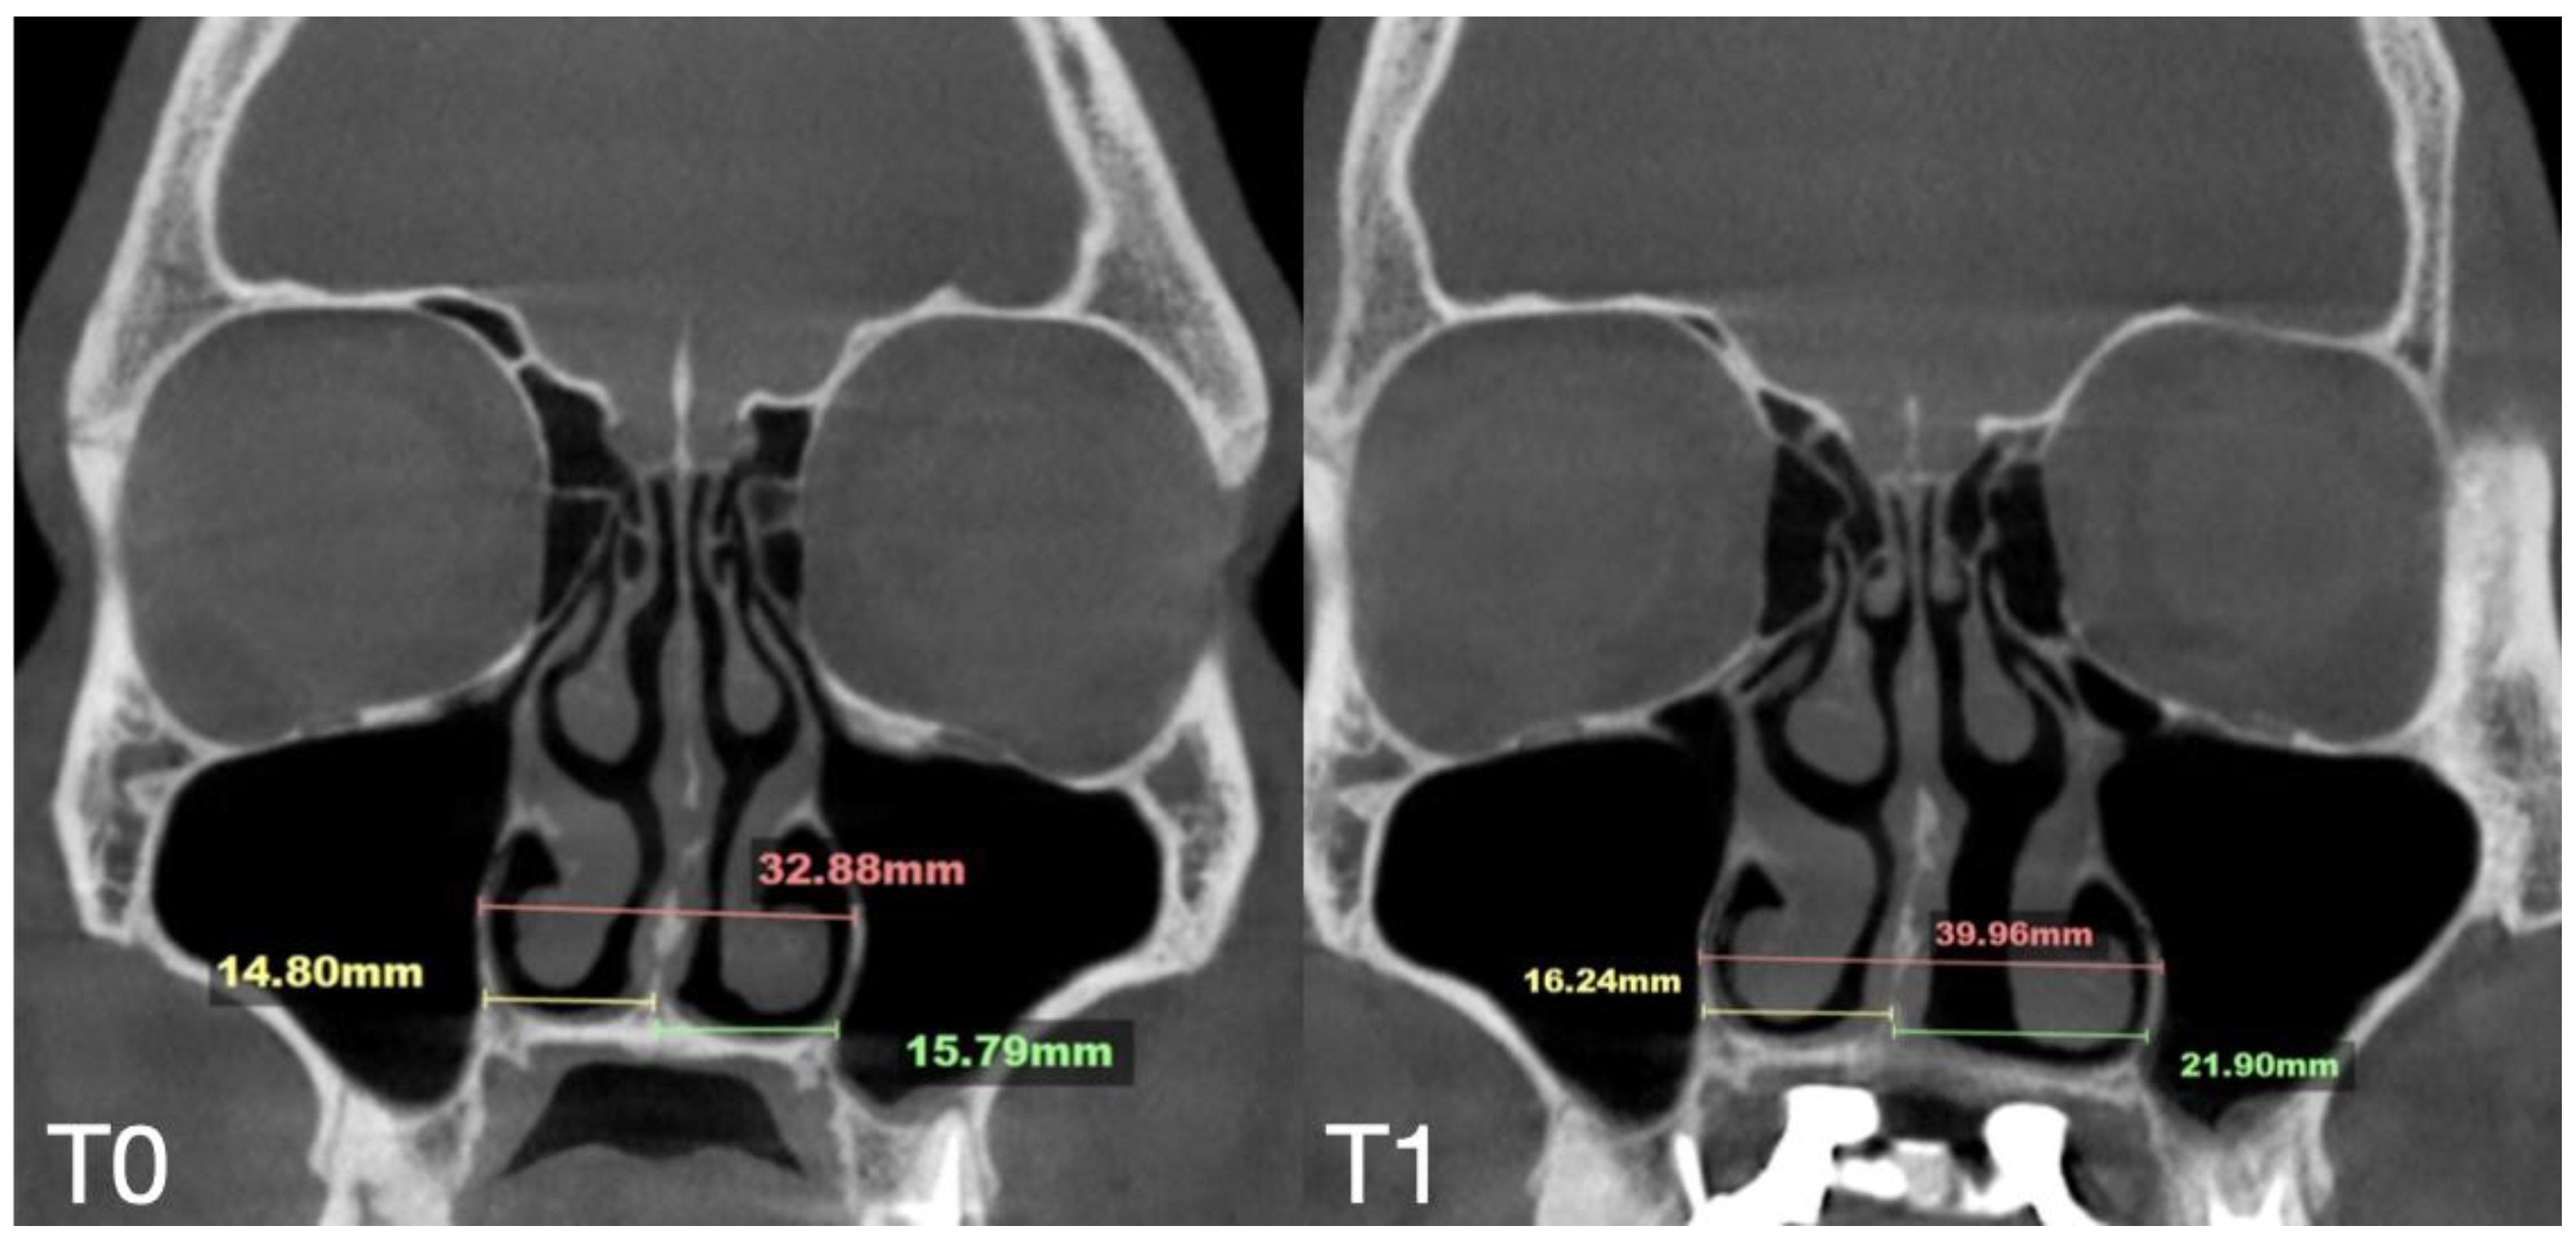

| Nasal Base Width, mm | Maxillary Base Width, mm | Lateral Nasal Width, mm | Inter-Pterygoid Distance, mm | Midpalatal Suture Separation, mm | |||||||||

|---|---|---|---|---|---|---|---|---|---|---|---|---|---|

| T0 | T1 | T2 | T0 | T1 | T2 | T0 | T1 | T2 | T0 | T1 | T2 | T1 | |

| Case A | 30.84 | 38.15 | 38.37 | 59.22 | 66.37 | 67.11 | 32.8 | 39.33 | 39.48 | 28.01 | 32.88 | 33.38 | 10.5 |